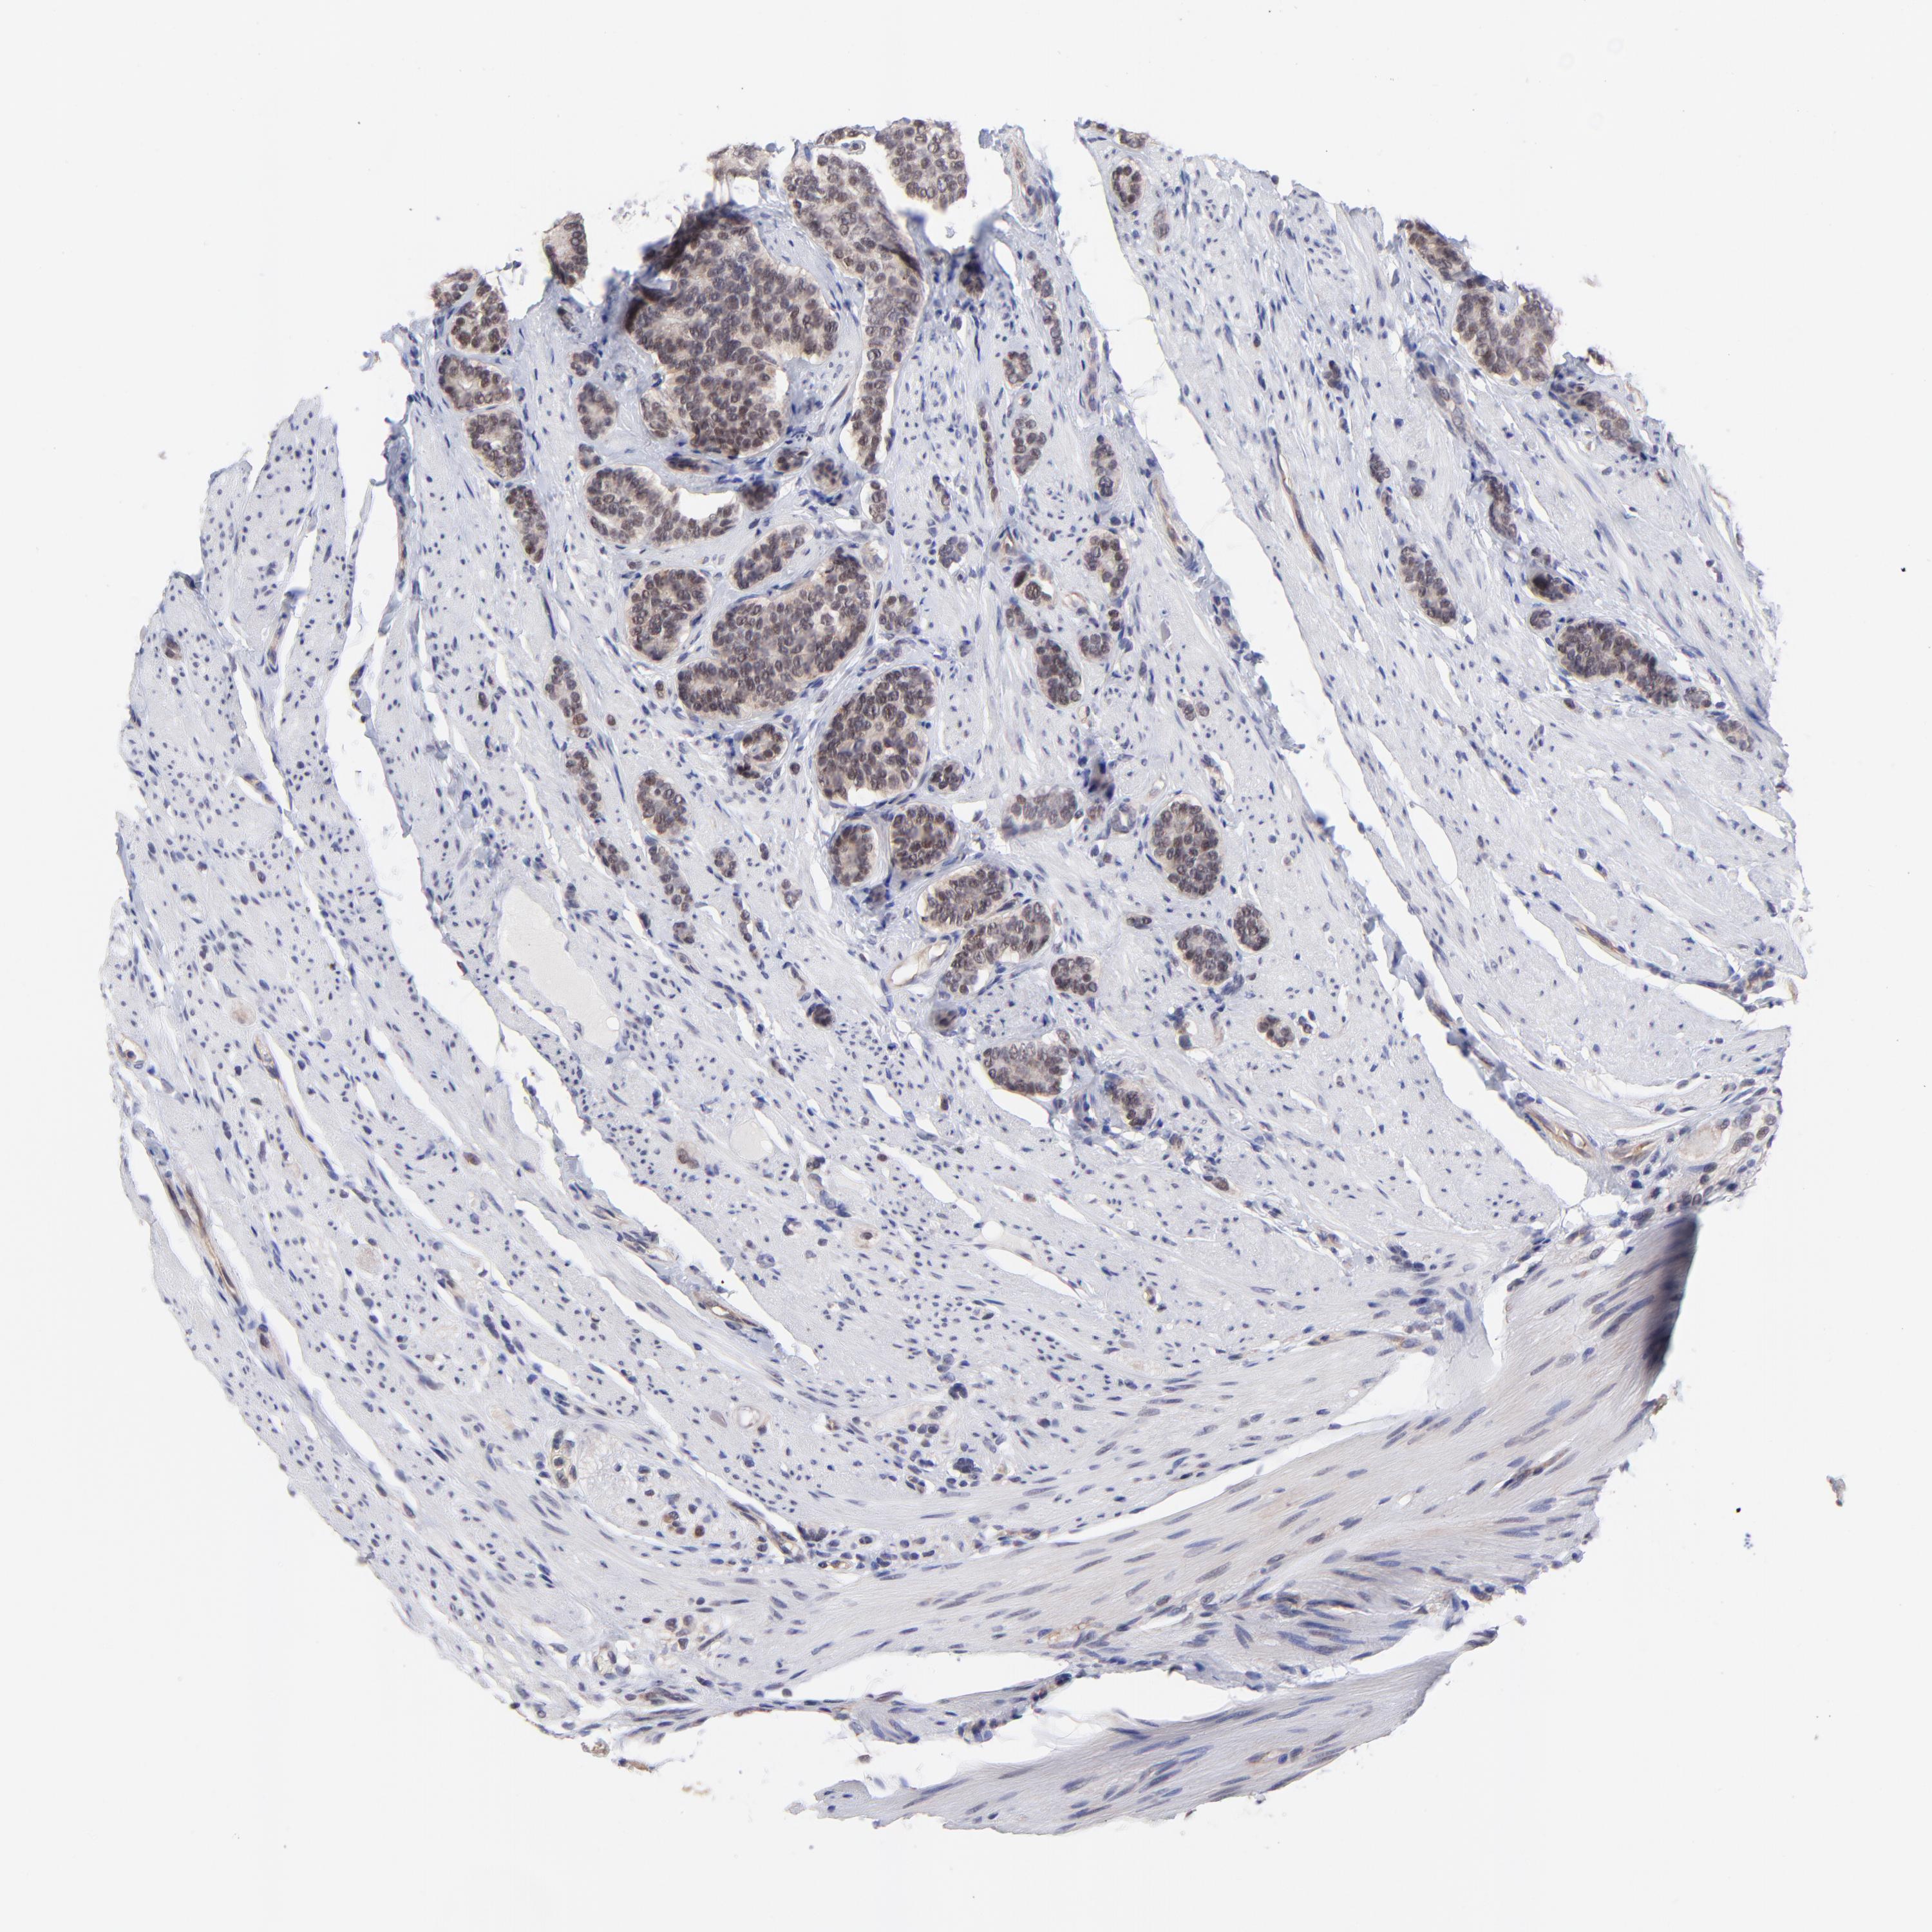

CARCINOID - Protein expressioni

A mouse-over function shows sample information and annotation data. Click on an image to view it in a full screen mode. Samples can be filtered based on level of antibody staining by selecting one or several of the following categories: high, medium, low and not detected. The assay and annotation is described here.

Antibody stainingi

Antibody staining in the annotated cell types in the current human tissue is reported as not detected, low, medium, or high, based on conventional immunohistochemistry profiling in selected tissues. This score is based on the combination of the staining intensity and fraction of stained cells.

Each image is clickable and will lead to virtual microscopy that enables deeper exploration of all samples and also displays staining intensity scores, fraction scores and subcellular localization as well as patient and tissue information for each sample.

Antibody HPA003203

Staining

High

Medium

Low

Not detected

Intensity

Strong

Moderate

Weak

Negative

Quantity

>75%

75%-25%

<25%

None

Location

Nuclear

Cytoplasmic/membranous

Cytoplasmic/membranous,nuclear

Carcinoid, malignant, NOS